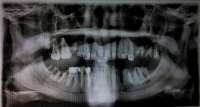

14732511028450.jpg (440Кб, 1866x1140)

14732511028541.jpg (378Кб, 2068x1160)

14732511028612.jpg (939Кб, 3060x1640)

>>513992

ОПТГ восьмимесячной давности. Сейчас всё, по идее, хуже уже. Но свежее снимка нету.

>>514011

"Единички" - это один зуб-один имплант? Ну да. Это мне предлагают в каждой первой клинике. Но я нищехуй и у меня нет и не будет сумм 1-1,5+ ляма, как они мне насчитывают. Нет, свалить на полгода-год из ДС лечить где подешевле тоже не могу.

Про all-on-4 потому и спрашиваю, что оно дешевле, и на это 300-600К бабла, вроде, кое-как наскрести можно попробовать. Но ссу того, что дешевый сыр бывает в мышеловке.